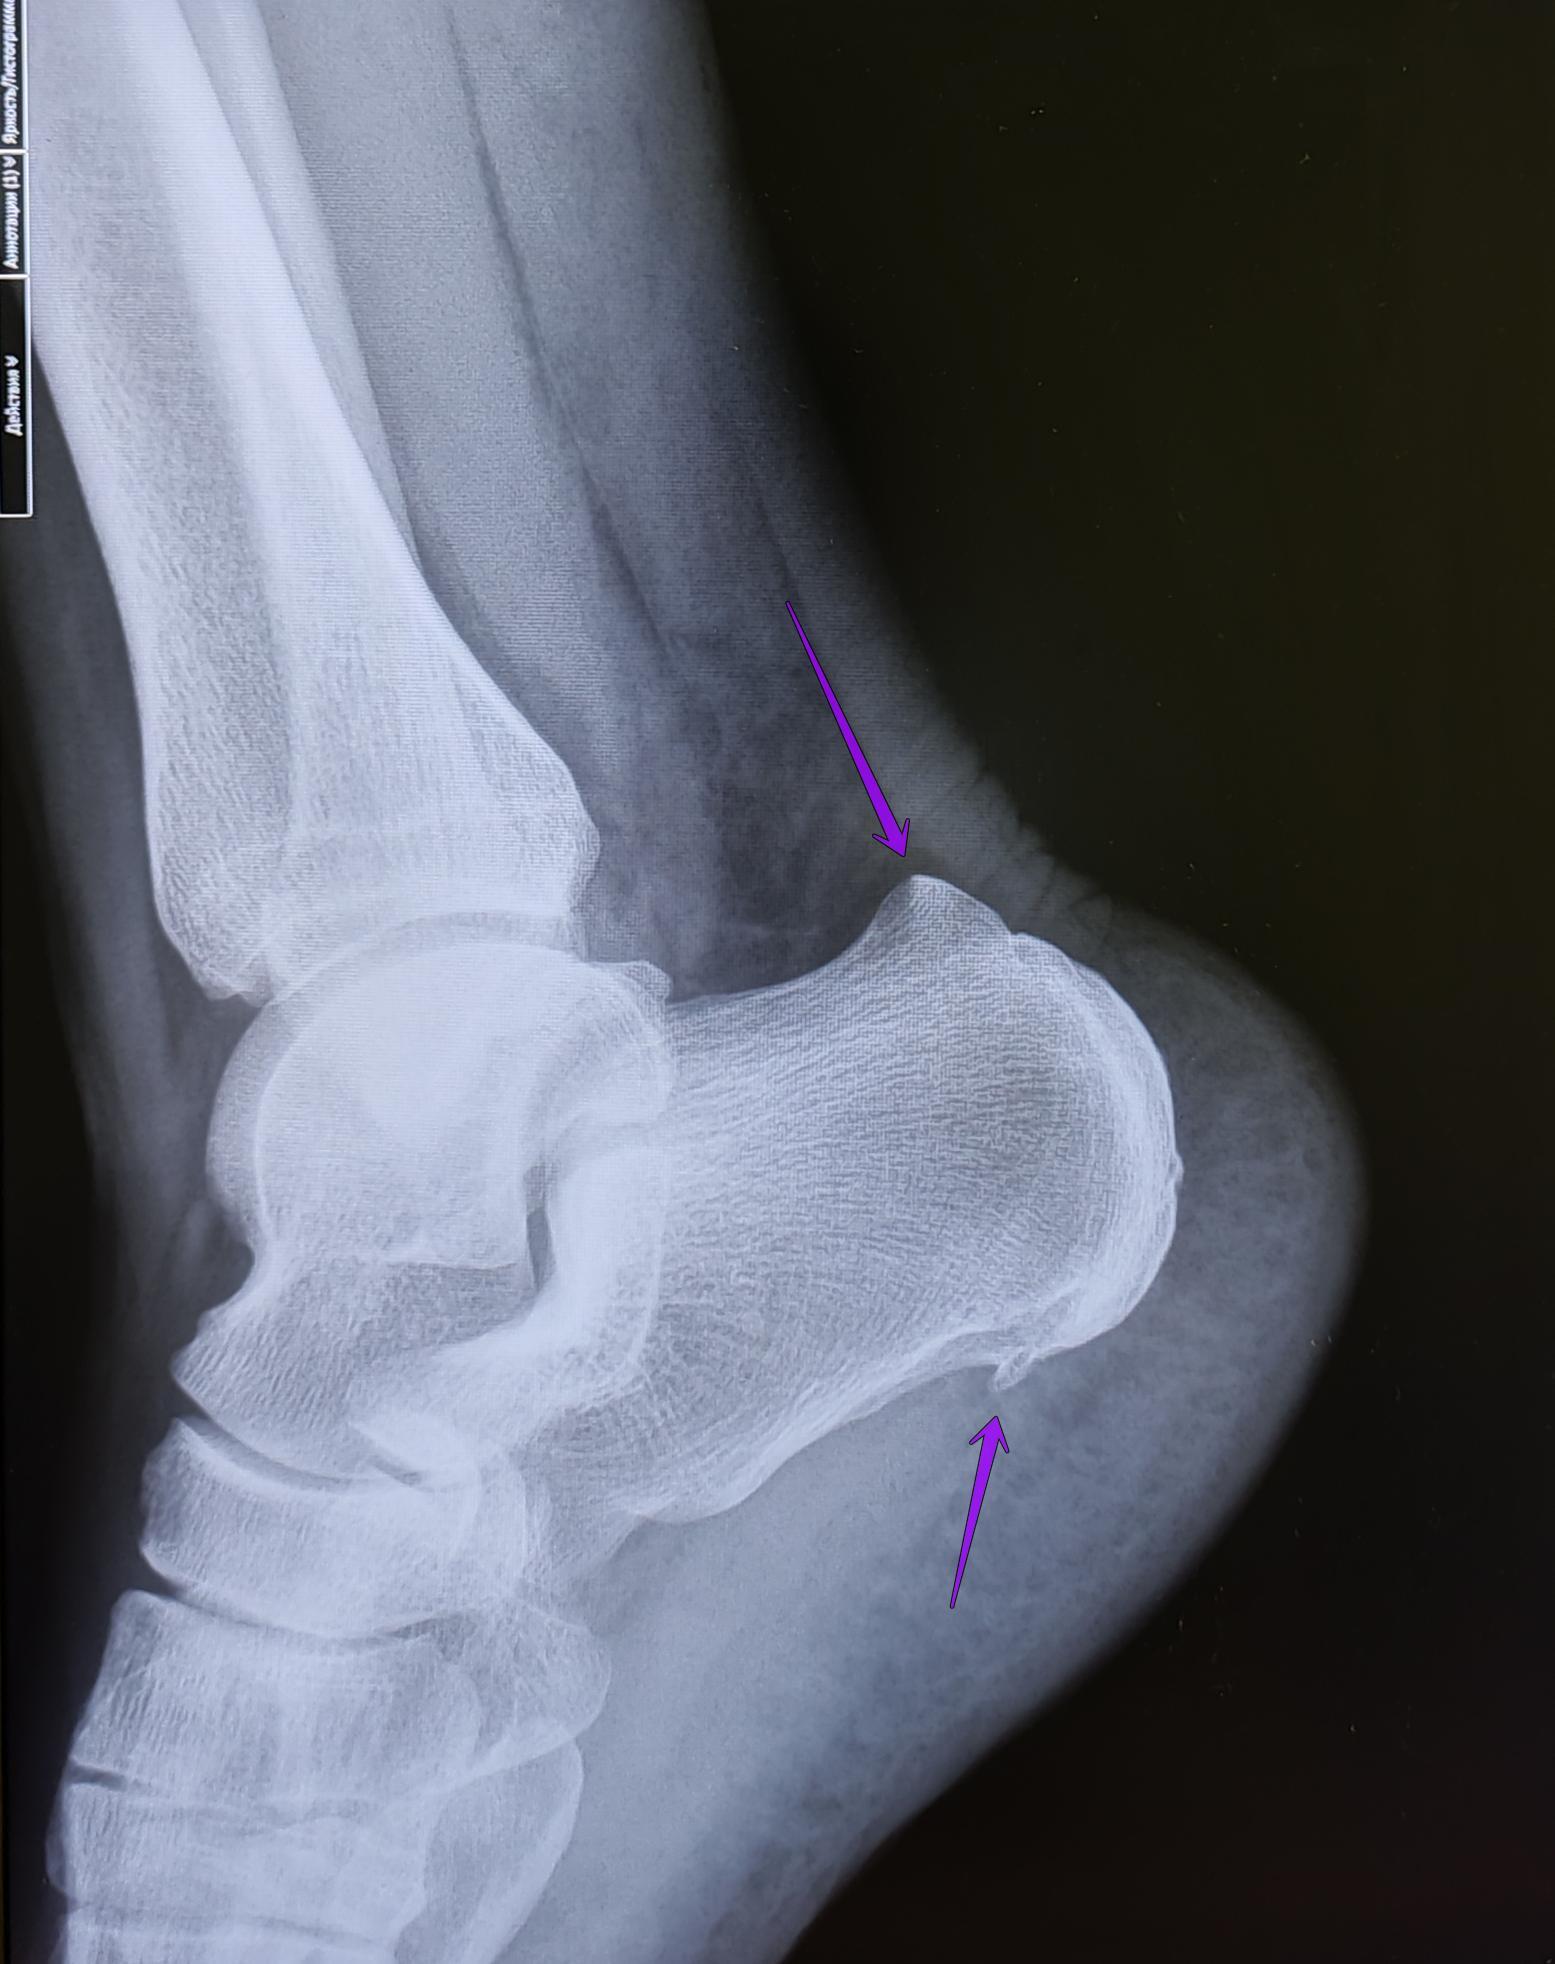

Описание: на Р-граммах правой и левой пяточных костей-травматических, деструктивных изменений не выявлено, структура костной ткани не изменена. В месте прикрепления подошвенных апоневрозов к буграм пяточных костей-визуализируются костные экзостозы. Верхняя часть бугров пяточных костей увеличена в размерах, имеет треугольную форму на широком основании. Заключение: Двусторонняя деформация Хаглунда. Двусторонние пяточные "шпоры".

При отсутствии длительного анамнеза воспалительного процесса, частых обращений с болевым синдромом, стац. лечения по поводу болевого синдрома, решение выносится на основании ст.65(Хирургические болезни и поражения костей, крупных суставов, хрящей:) г, Б-3:призывник годен к военной службе с незначительными ограничениями.